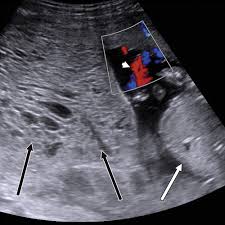

Ultrasound remains the radiological investigation of choice for initial.

The latter four entities are referred to as gestational trophoblastic neoplasia GTN. A common characteristic of all gestational trophoblastic disease is an abnormal proliferation of trophoblast but different components predominate in different tumors. Ultrasound remains the radiological investigation of choice for initial. Gestational trophoblastic neoplasia GTN encompasses a broad spectrum of placental lesions from the pre-malignant hydatidiform mole complete and partial through to the malignant invasive mole choriocarcinoma and rare placental site trophoblastic tumour PSTT. The latter four entities are referred to as gestational trophoblastic neoplasia GTN. There are several histologically distinct types of GTD that range from premalignant complete and partial hydatidiform moles HMs to malignant diseases also known as gestational trophoblastic. Ultrasound in the Diagnosis and Management of GTN Gestational trophoblastic neoplasia GTN includes invasive mole choriocarcinoma PSTT and ETT. Because it is an unusual and serious disease that affects women of reproductive age as well as because its appropriate treatment results in high cure rates it is crucial that radiologists be familiar with gestational trophoblastic disease in order to facilitate its early diagnosis and to ensure appropriate follow-up imaging. Gestational trophoblastic disease GTD is a spectrum of both benign and malignant gestational tumors including hydatidiform mole complete and partial invasive mole Choriocarcinoma placental site trophoblastic tumor and epithelioid trophoblastic tumor.